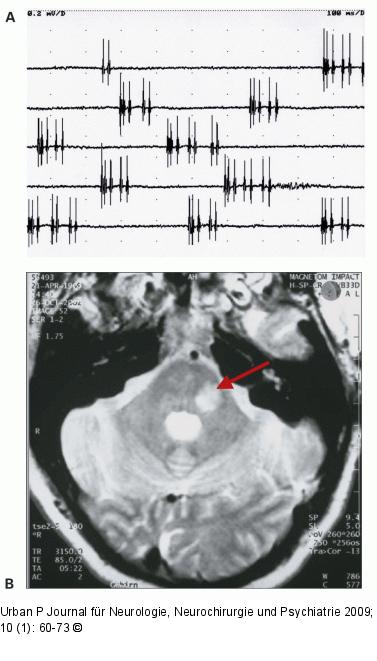

Abbildung 8a-b: Fazialis-Myokymie Fazialis-Myokymie. (a) Ableitung mit konzentrischer Nadel-elektrode aus dem M. orbicularis oris links. Auftreten spontaner Entladungsserien (Doublets, Multiplets). (b) MRT: Demyelinisierungsherd im Kleinhirnbrückenstiel im Verlauf des intramedullären N. facialis links. |

Fazialis-Myokymie. (a) Ableitung mit konzentrischer Nadel-elektrode aus dem M. orbicularis oris links. Auftreten spontaner Entladungsserien (Doublets, Multiplets). (b) MRT: Demyelinisierungsherd im Kleinhirnbrückenstiel im Verlauf des intramedullären N. facialis links. |